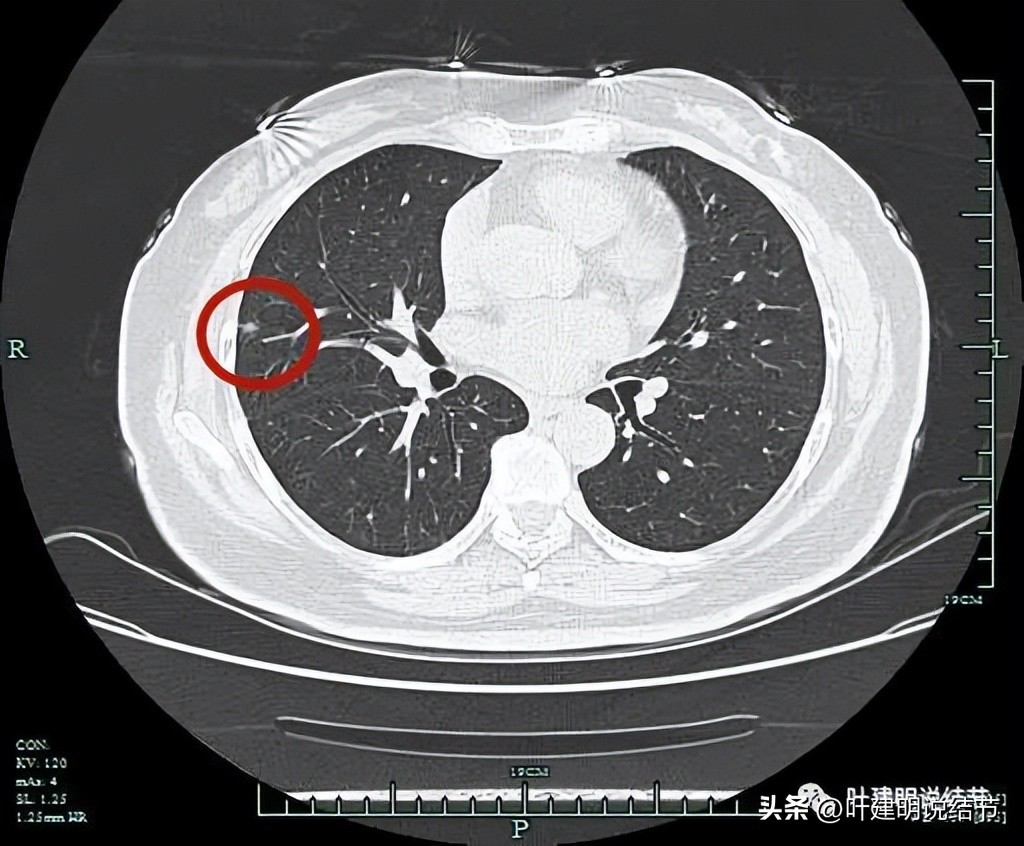

某A,女性,57岁,其于12年前曾因“子宫内膜癌”行手术治疗,此后每年均规律体检复查,前段时间复查时发现右肺实性结节,报告示“右肺中叶胸膜下类结节灶,较前新见,转移可能,建议随访复查”。我们来分析一下这样的病例怎么来进行临床决策与考虑。

病灶出现,边缘稍偏糊

右中叶这个病灶,虽然有毛刺、血管征、胸膜牵拉等偏向恶性的征象,但却边缘相对平直、边上有条索状、密度不均而灶内中间的密度偏低,一年前此处没有异常病灶。总体上感觉更符合良性结节,恶性虽不能除外,但可能性小些。